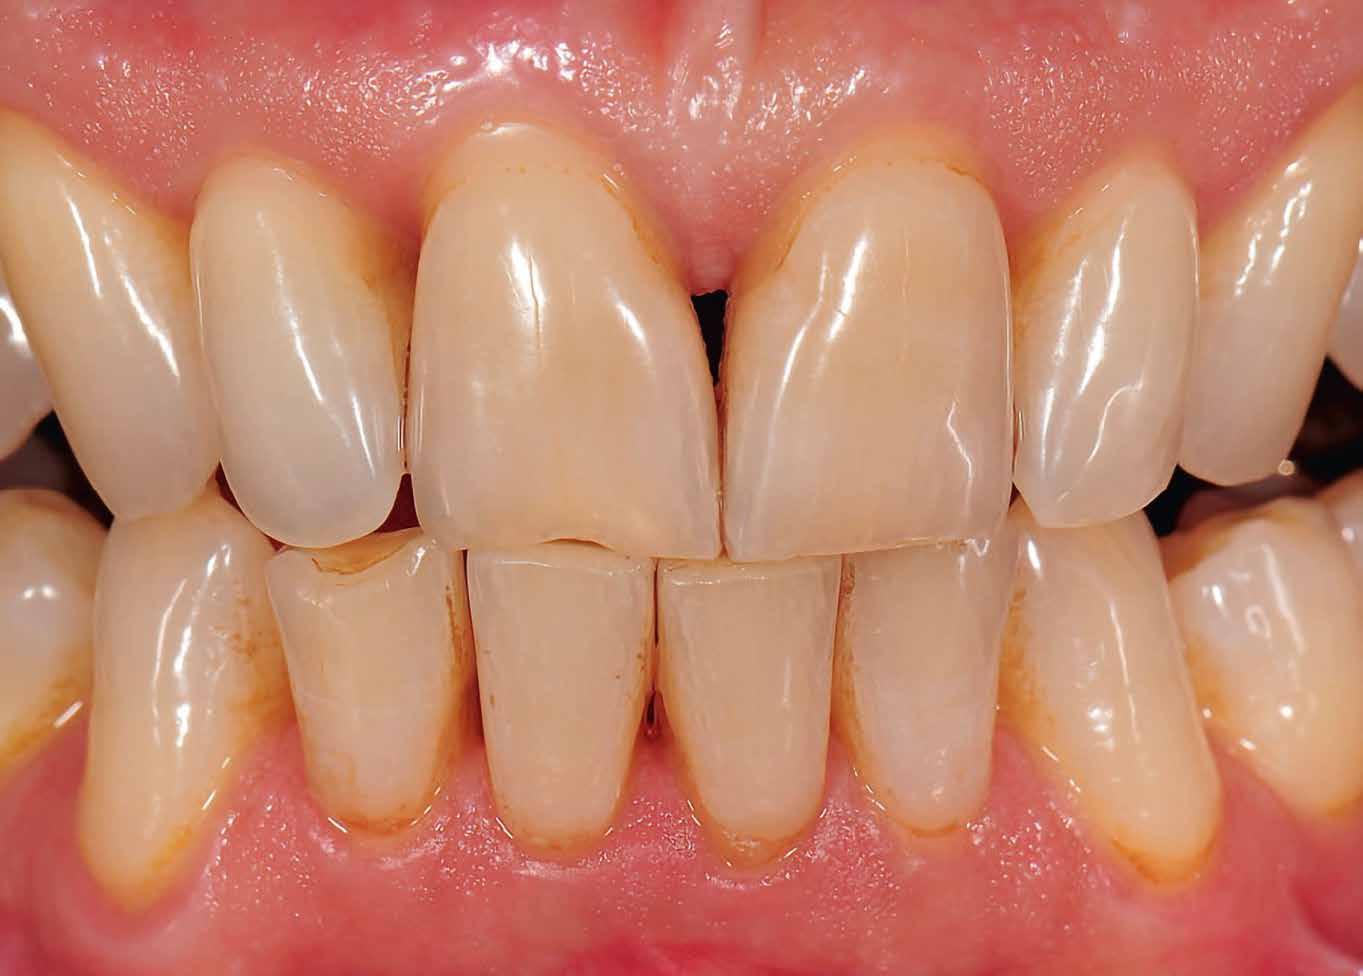

Interdiszciplináris fogászati kezelés myofunkcionális készülék, alignerek és protetikai ellátás alkalmazásával

MED. DENT Abradált frontfogakkal rendelkező felnőtt páciens interdiszciplináris kezelése